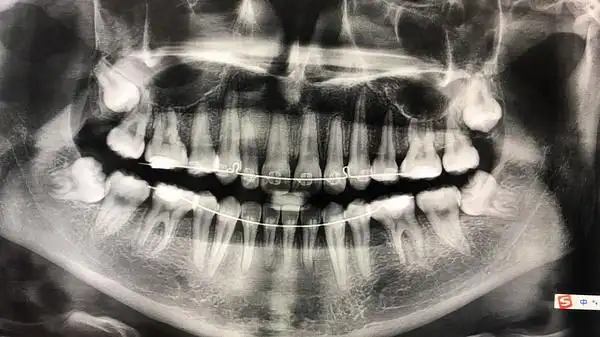

本人女28岁牙齿整齐但有深覆合深覆盖拍过牙片做过牙模

后续 掉的应该是牙齿?牙片能看出有没蛀牙嘛